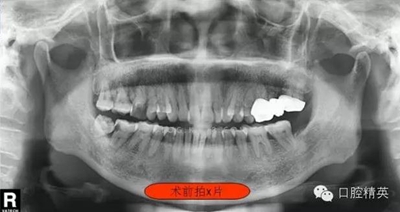

右下7根管治療(C型) 科貿(mào)嘉友收錄

這位患者女性,年齡60歲。遠(yuǎn)中鄰面深齲,探診疼痛不適。主訴有夜間疼痛加重,叩診(+),一度松動(dòng),遠(yuǎn)中根部牙槽骨吸收,診斷牙髓炎。后來(lái)右下8拔除。